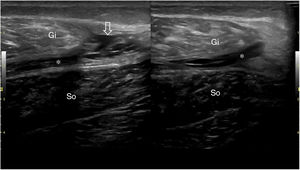

El músculo sano, ecográficamente, presenta una ecogenicidad inferior a la del tejido celular subcutáneo y una disposición de finas líneas paralelas ecogénicas, múltiples, en cortes longitudinales, en «pluma de ave» (fig. 1), y aspecto reticular en corte transversal «aspecto moteado» (fig. 2), rodeados por la fascia hiperecogénica y en su interior la unión miotendinosa también hiperecogénica4. En ecografía se describen 4 grados de lesión muscular propuestos por Peetrons en 20027 (tabla 2).